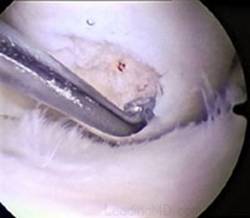

Chirurgul trebuie sa fie foarte atent atunci cand examineaza posteriorul condililor femurali. Daca se semnaleaza orice vatamare/rana/deteriorare pe suprafetele articulare, trebuie sa se cerceteze atent calitatea cartilajului. Orice flapsuri instabile sunt inlaturate prin folosirea unui aparat de ras electric artroscopic sau curette. Apoi, un curette este folosit pentru a debrida stratul de cartilagiu calcifiat de la baza in toata grosimea defectului. Acest pas se bazeaza pe activitatea lui Frisbi, care a demonstrat vindecarea suprafetei articulare superioare la un cal, cand stratul cartilagiului calcifiat este indepartat. Cand indepartam stratul cartilajului calcifiat, in general nu se foloseste un aparat de ras. Cu un aparat de ras este dificil de controlat cantitatea de os eliminat, si este posibil ca osul subcondral sa fie afectat.

Dupa indepartarea cu succes a stratului de cartilaj calcifiat, o andrea este folosita pentru a face mai multe gauri mici (mirofracturi) in osul expus al defectului condral aflate la distanta de 1-2 mm. Trebuie lasata o punte de oase potrivita intre gauri. Tehnica de microfracturi are numeroase avantaje fata de foraj. Mai intai de toate, creaza o leziune termala mai mica. Mai mult, cu microfracturi chirurgul este capabil sa intre in zonele dificile ale suprafetei articulare cu un control mai bun asupra adancimii de patrundere. La finalizarea microfracturii, o suprafata aspra este generata pentru aderenta cheagului de sange care contine celule mezenchimale nediferentiate de la osul subcondral. Trebuie avut grija ca cele mai marginase parti ale leziuni sa fie patrunse de andrea pentru a ajuta la vindecarea tesutului reparator la imprejmuirea suprafetei articulare. Odata ce microfractura este finalizata, pompa artroscopica este oprita pentru a se asigura ca sangerarea maduvei curge din gaurile mici umpland defectul.[54]

Debridarea (a, b, c).

Fig.25.a. Debridarea. Fig.25.b. Microfracturare.